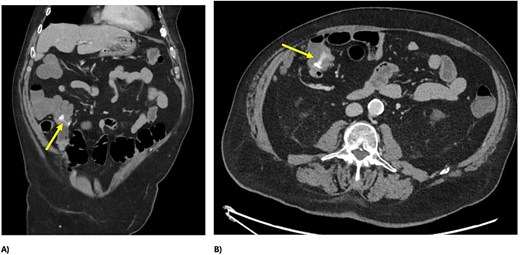

A 73 year-old male presented to our tertiary hospital with a three day history of major colonic bleeding, while on therapeutic warfarin for a metallic aortic valve. Other medical history included laparoscopic cholecystectomy, Parkinson’s disease, and a normal colonoscopy 12 months prior. Computed tomographic mesenteric angiography demonstrated active contrast pooling within the caecum and appendiceal base (Fig. 1). He underwent successful interventional radiology guided angioembolization of a branch of the ileocolic artery, using a gel embolic injection (Fig. 2).

CT demonstrating active bleeding pre-embolization, with pooling of contrast in the caecum and appendiceal base; (A) axial view and (B) coronal view.